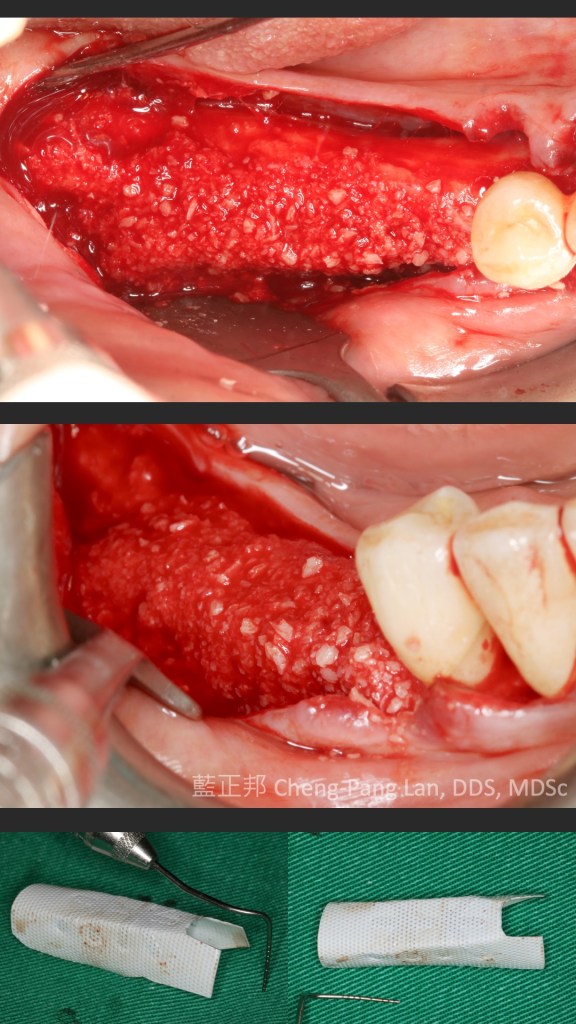

●第十一章垂直補骨,前一版的作者Massimo Simion,改成了Istvan Urban,果如我2016年判斷的,Istvan Urban已成為垂直補骨的接班人,連主編Buser也這麼認為(笑)。這邊寫的是簡易版,若朋友有興趣詳細的垂直補骨,直接看Urban寫的兩本垂直補骨書即可,我這邊也有第二本Vertical 2心得。但是十一章關於頰側與舌側的皮瓣鬆弛,寫得簡潔扼要,值得詳讀。

●第十四章補骨病發症,Isabella Rocchietta當年待過Massimo Simion的團隊內,有不少不可吸收再生膜併發症的處理經驗,這篇雖然文字多,但寫得很完整。Rocchietta的能力很強,把文獻整理非常好,從手術前就要考量的因素,到手術中,手術後都有。同時也有新的不吸收再生膜暴露的處理分類,自己看了蠻有收穫,同時,從最後的引用文獻,再回推思考為何Rocchietta引用?很有意思。